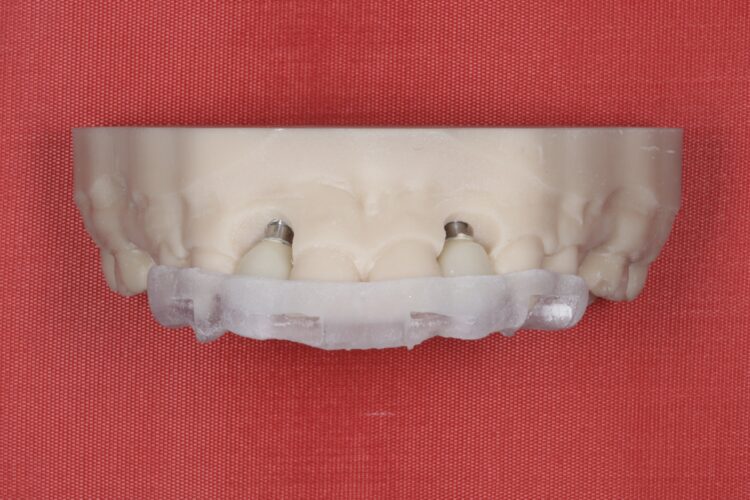

Post-surgical healing and impressions (August 2023)

A week after the surgery, the patient was seen for a healing review, during which X-rays were taken and sutures were removed. After sufficient healing, the patient returned for an impression appointment, where the temporary teeth were removed and scans were taken to fabricate the final crowns.